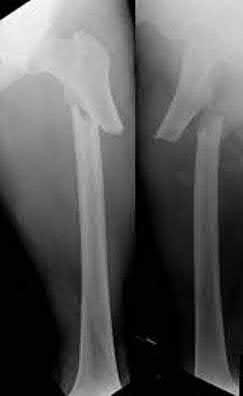

A 12-year-old boy presents with left thigh pain, an antalgic gait, and an externally rotated left lower extremity. Radiographs demonstrate the pathology shown. Which of the following is considered an absolute indication for prophylactic pinning of the asymptomatic, contralateral hip in a patient presenting with Slipped Capital Femoral Epiphysis (SCFE)?

Correct Answer: Underlying endocrine disorder (e.g., hypothyroidism)

Explanation:

SCFE is characterized by a displacement of the proximal femoral epiphysis. Prophylactic pinning of the contralateral hip is somewhat controversial but generally recommended in patients with a high risk of subsequent contralateral slip. Absolute indications or highly strong recommendations for prophylactic contralateral pinning include an underlying endocrine disorder (such as hypothyroidism or growth hormone deficiency), renal osteodystrophy, previous radiation therapy, and presentation at a very young age (e.g., < 10 years). Endocrine disorders dramatically increase the risk of bilateral involvement, often occurring simultaneously or sequentially.